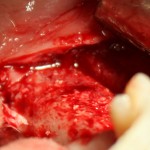

Например, в следующей ситуации:

Оставить так, как есть — это значит, сильно рисковать имплантом и объемом альвеолярного гребня — фактически, большая часть импланта пятого зуба «висит в воздухе». Поэтому получившуюся костную полость мы заполняем аутокостной стружкой в смеси с Bioss и закрываем коллагеновой мембраной BioGide:

При необходимости, мембрану можно фиксировать пинами.

Через три месяца результат:

можно ставить формирователи и заканчивать лечение: